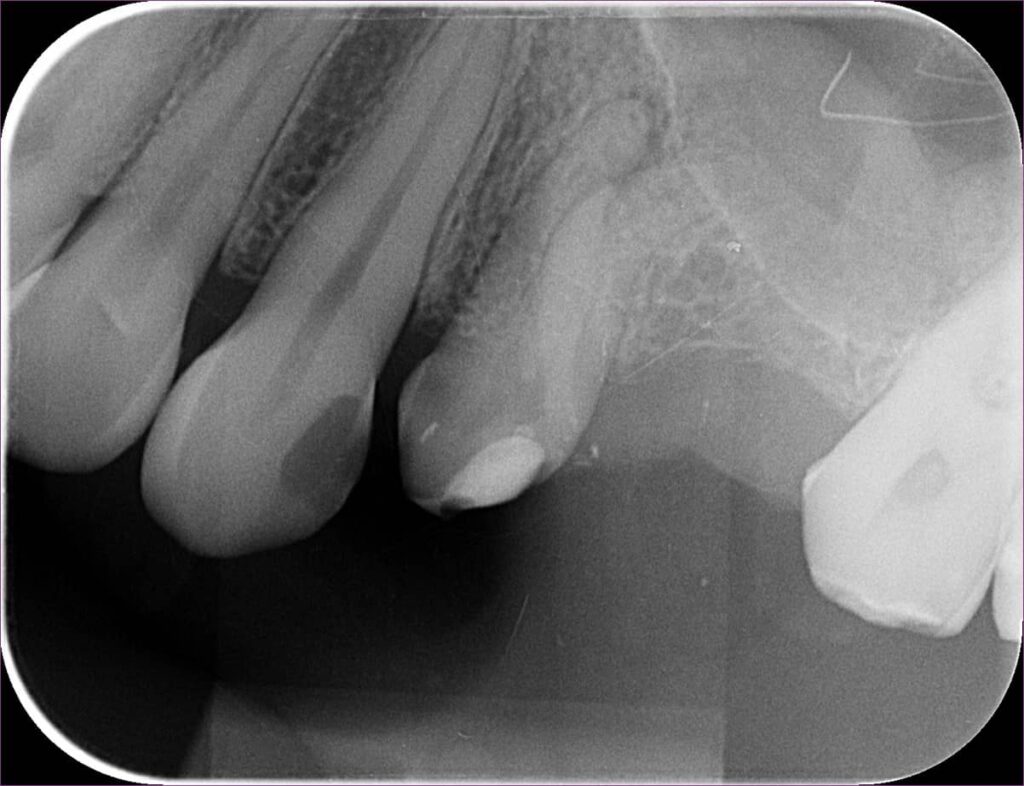

Ezen az utolsó képen látható a fog kontrollfelvétele. A gyökértömést követően a fogat üvegszálas-csapos megerősítéssel láttuk el, majd a gyökérkezelés menete az utolsó fázisához ért: a kezelőorvos beragasztotta az elkészült fogászati hidat.

Erre a fogra nyugodtan készülhet a pótlás: biztosak lehetünk abban, hogy a későbbiekben nem fog semmilyen panaszt okozni!

A helyes technikának, illetve a mikroszkópnak köszönhetően egy ilyen bonyolult csatornarendszerrel rendelkező fogat is meg tudtunk menteni, így a fogászati híd elkészítése előtt is elhárult minden akadály.